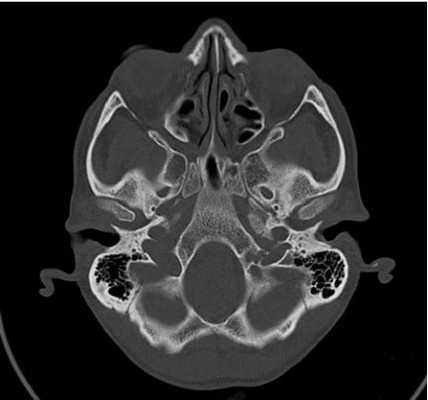

КТ основания черепа

КТ основания черепа - метод медицинской визуализации, основанный на использовании рентгеновских лучей, и применяющийся для диагностики патологических процессов, локализующихся в нижних отделах черепной коробки. Позволяет получать серии послойных снимков области интереса, толщиной от 0,5 мм, с высоким разрешением и четкостью. Благодаря этому компьютерная томография - один из самых точных и достоверных методов диагностики, незаменимый при некоторых патологиях и заболеваниях мозговой части черепа.

Что покажет КТ основания черепа

На снимках, полученных во время обследования, визуализируются анатомические и костные структуры основания черепа, включающие в себя основание мозга, ствол мозга, черепно-мозговые нервы, краниовертебральную область, область таламуса, гипоталамуса, гипофиза, турецкого седла, перекреста зрительных нервов. Исследуется нормальное строение вышеперечисленных анатомических образований, обнаруживаются участки с отклонениями от нормы в виде новообразований, кист, воспалительных процессов. Оценивается протяженность обнаруженных патологий, их связь с окружающими органами и тканями. Изучается влияние патологического процесса на функции ЦНС.